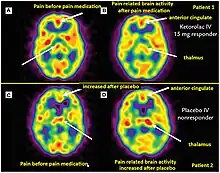

Positron emission tomography (PET) imaging in theranostics provides insight into metabolic and molecular processes within the body. The PET scanner detects photons and creates three-dimensional images that enable visualization and quantification of physiological and biochemical processes.[10] PET imaging uses radiotracers that target specific molecules or processes. For example, [18F] fluorodeoxyglucose (FDG) is commonly used to assess glucose metabolism, as cancer cells exhibit increased glucose uptake. Other radiotracers target specific receptors, enzymes, or transporters, allowing the evaluation of various physiological and pathological processes.[10]

PET imaging plays a role in both diagnosis and treatment planning. It aids in the identification and staging of diseases, such as cancer, by visualizing the extent and metabolic activity of tumors. PET scans can also guide treatment decisions by assessing treatment response and monitoring disease progression. Additionally, PET imaging is used to determine the suitability of patients for targeted therapies based on specific molecular characteristics, enabling personalized treatment approaches. [11]